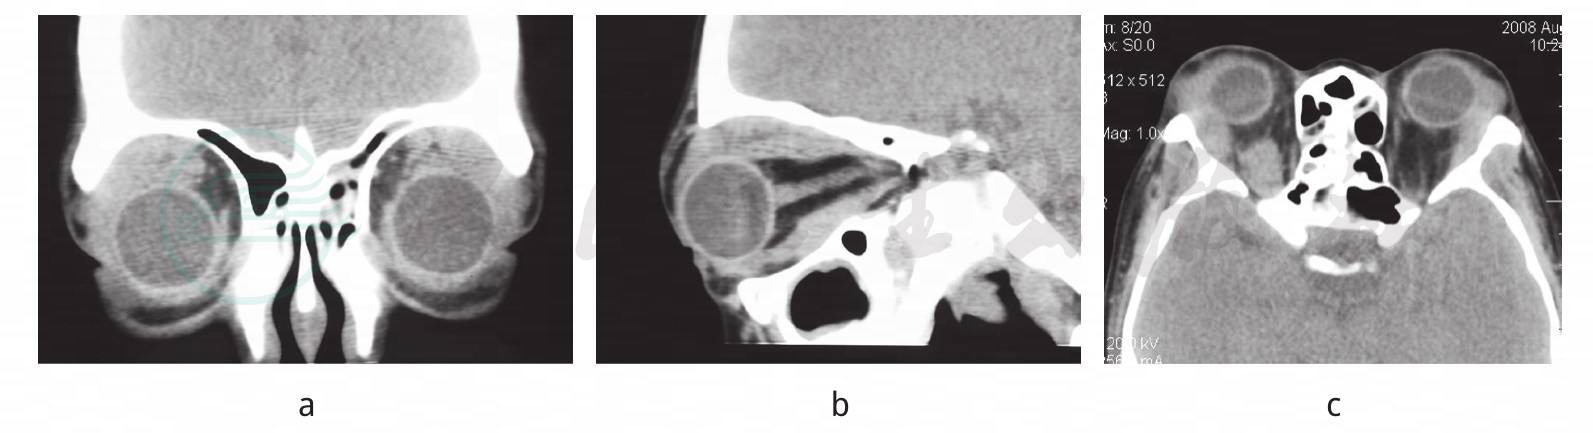

图1

a~c. 眼眶CT:双泪腺区软组织影,呈三角形沿眶壁及外直肌向眶尖蔓延,与眼外肌分界不清,眶骨壁未见明显破坏